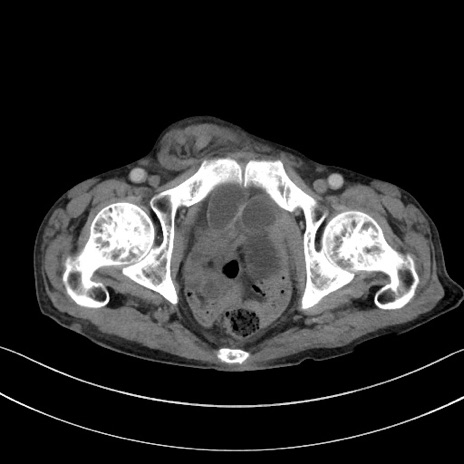

症例3(横断像)

【症例】 70歳代男性

【主訴】右鼠径部腫瘤、疼痛

【現病歴】本日朝より上記主訴あり、受診。

【既往歴】膀胱癌にて膀胱全摘、両側尿管皮膚瘻

【データ】WBC 5600、CRP 0.56